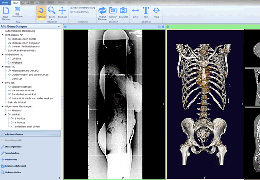

BrainVoyager starts by automatically assembling images into 2D and 3D functional and anatomical multi-slice projects.

Data analysis includes preprocessing, correlation analysis, determination of Talairach coordinates, volume rendering, surface rendering and cortex flattening.

Segmentation

Segmentation of tissue (e.g., isolating the brain, differentiating gray and white matter) is performed using region-growing methods, filter operations as well as the application of 3D templates. Using the mouse it is very easy to explore a 3D volume with superimposed pseudocolor-coded statistical maps in a four-window representation showing a sagittal, coronal, transversal and oblique section. Based on a (segmented) 3D data set a three-dimensional reconstruction of the subjects' head and brain can be calculated and displayed from any specified viewpoint using volume or surface rendering.

Volume Rendering

Volume rendering is performed with a very fast ray casting algorithm; lightning calculations are based on Phong-shading. Surface rendering of reconstructed surfaces is performed using OpenGL. Using texture mapping, a reconstructed surface (e.g., head or brain) may be sliced in real time, showing both surface and volume data at the same time. Initial polygon meshes serve as the basis for surface finding, cortex inflation and cortex flattening computations.